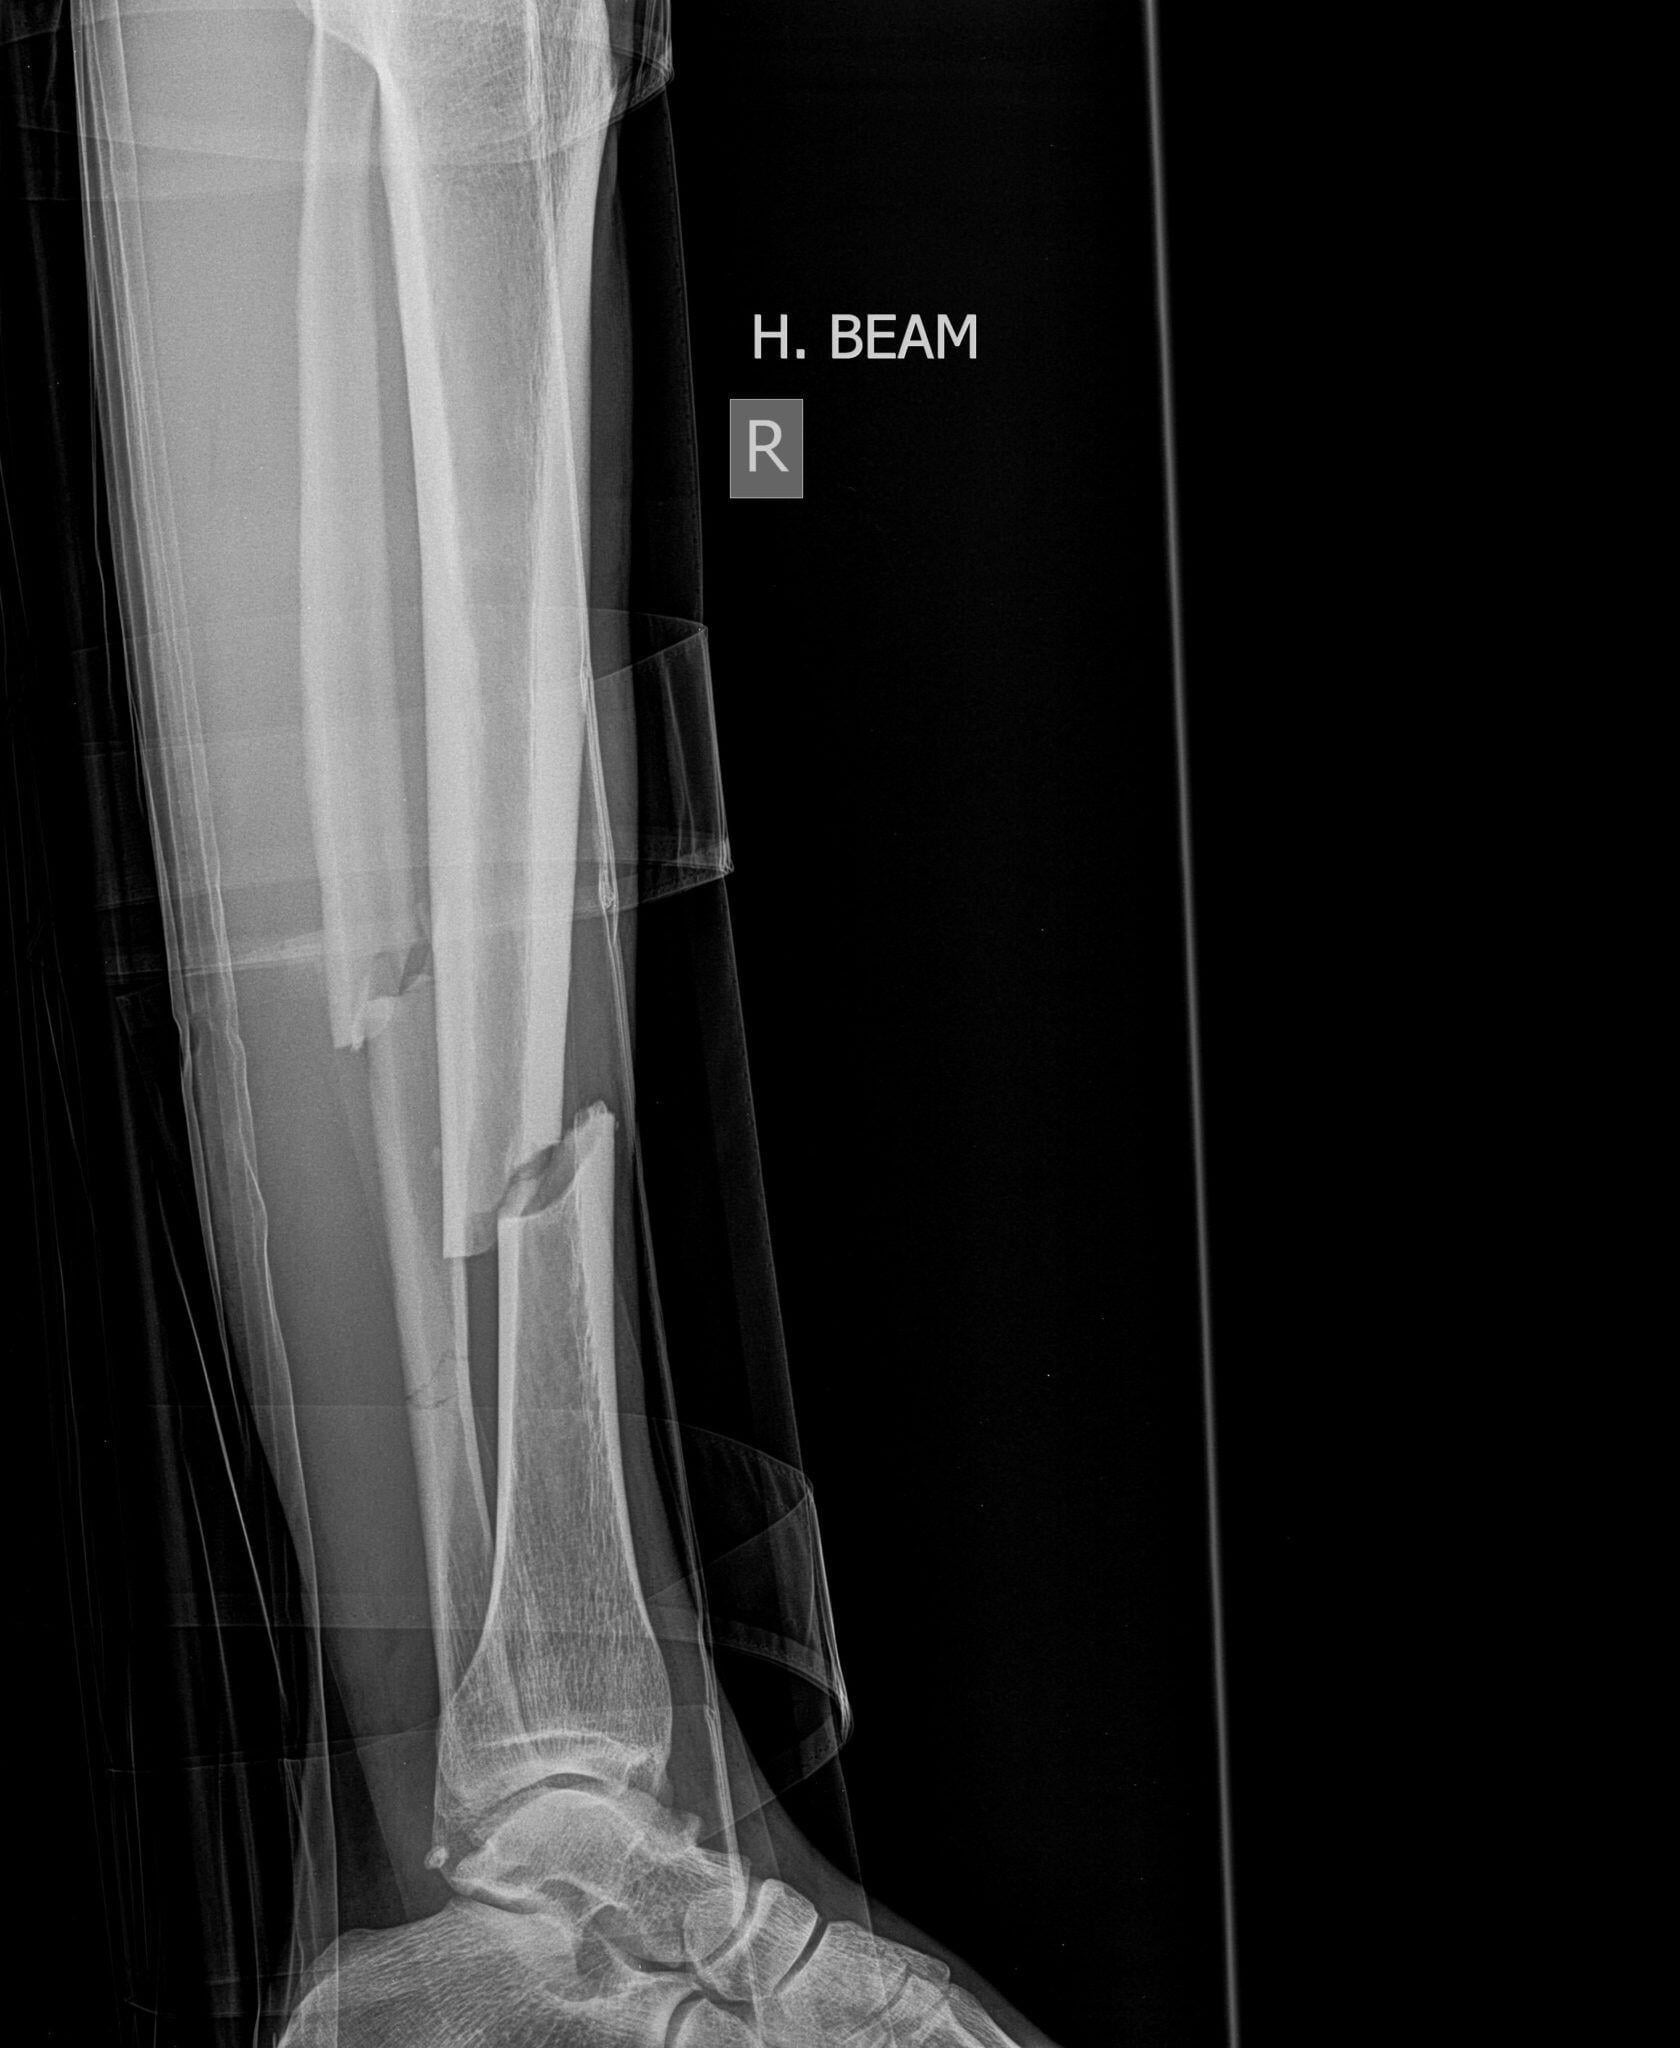

Bone Fracture Healing

Despite its mineral strength, bones can crack or even break if subjected to extreme...